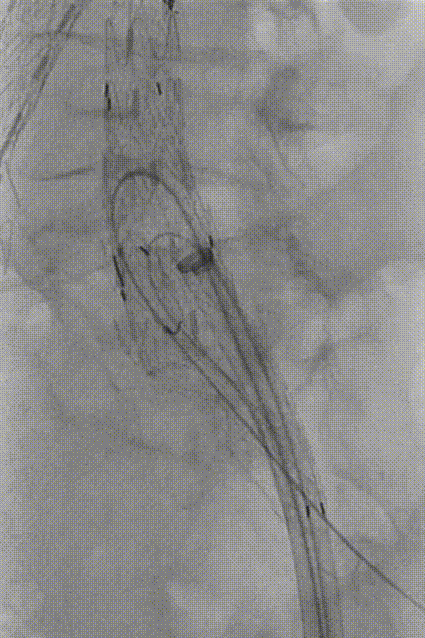

保留Amplatz导丝,于体外将260cm软泥鳅导丝置入GORE髂动脉分支型覆膜血管内支架CEB231010(23mm-10mm-100mm)中,形成牵张通道,沿GORE 20Fr鞘植入IBE主体支架,退鞘至短腿下方,于目标位置释放至短腿打开,再次退鞘至长腿远端,释放IBE主体支架长腿。

gore医疗怎么样「漫腹精论」独具匠心 推陈出新——同侧IBE支架内翻山重建髂内动脉治疗EVAR术后内漏病例报道_https://www.jmylbn.com_新闻资讯_第14张

释放IBE主体到短腿

gore医疗怎么样「漫腹精论」独具匠心 推陈出新——同侧IBE支架内翻山重建髂内动脉治疗EVAR术后内漏病例报道_https://www.jmylbn.com_新闻资讯_第15张

释放IBE主体到长腿

将20Fr鞘沿泥鳅导丝硬头端送至IBE主体支架分叉处,再导入GORE DSF1245鞘经20Fr鞘沿泥鳅导丝翻山至短腿开口。

gore医疗怎么样「漫腹精论」独具匠心 推陈出新——同侧IBE支架内翻山重建髂内动脉治疗EVAR术后内漏病例报道_https://www.jmylbn.com_新闻资讯_第16张

翻山至IBE短腿开口